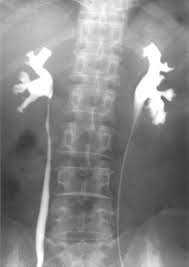

رنگی (Color X-ray)

پرتونگاری رنگی یا با کنتراست رنگی از مواد کنتراست خاص برای افزایش وضوح تصویر استفاده میکند. این مواد معمولاً حاوی یونهای ید یا باریم هستند که در بدن بیمار تزریق یا بلعیده میشوند. این مواد کنتراست کمک میکنند تا قسمتهای خاصی از بدن مانند دستگاه گوارش، عروق و ریهها بهطور واضحتری دیده شوند.ویژگیها:

استفاده از مواد کنتراست که در بدن بیمار وارد میشود تا تصاویر دقیقتری ایجاد کند.

تصاویر بهطور معمول رنگی به نمایش در میآیند.

قادر به نشان دادن جزئیات بیشتر از تصویربرداری ساده.

شناسایی ناهنجاریها در سیستم عروقی و مثانه.

بررسی دستگاه گوارش: میتواند به شناسایی مشکلات مربوط به سیستم گوارشی مانند جسم خارجی یا انسداد روده کمک کند.